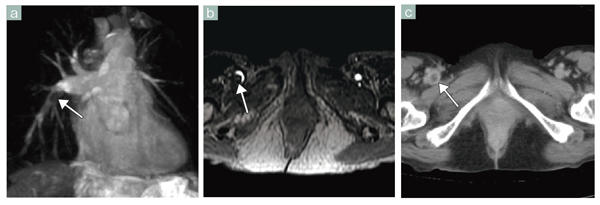

■症例2 Inhanceによる非造影MRA(肺動脈)

a:Inhance inflow IR法による肺動脈撮像をMIP処理で表示。右肺動脈(中間~肺底動脈幹)に陰影欠損(←)が認められ,肺動脈血栓症と診断された。

b:同患者,同日のMR Venography。

c:同部位の造影CT画像。右大腿静脈に血栓(↑)が観察される。